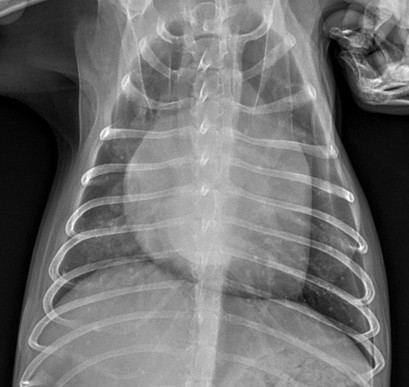

Stage D 강아지 심장병심장병 D단계 포메라니안, 이뇨제 내성으로

반응 저하를 극복한 맞춤 치료 케이스 -

폐성고혈압 우심부전갑작스러운 식욕부진과 켁켁거림,

폐성고혈압으로 인한 우심부전이었습니다. -

호흡곤란 고양이 비대성 심근병증개구호흡과 저체온 증상으로 응급내원!

유전적 요인의심장병, 혈전 예방치료까지